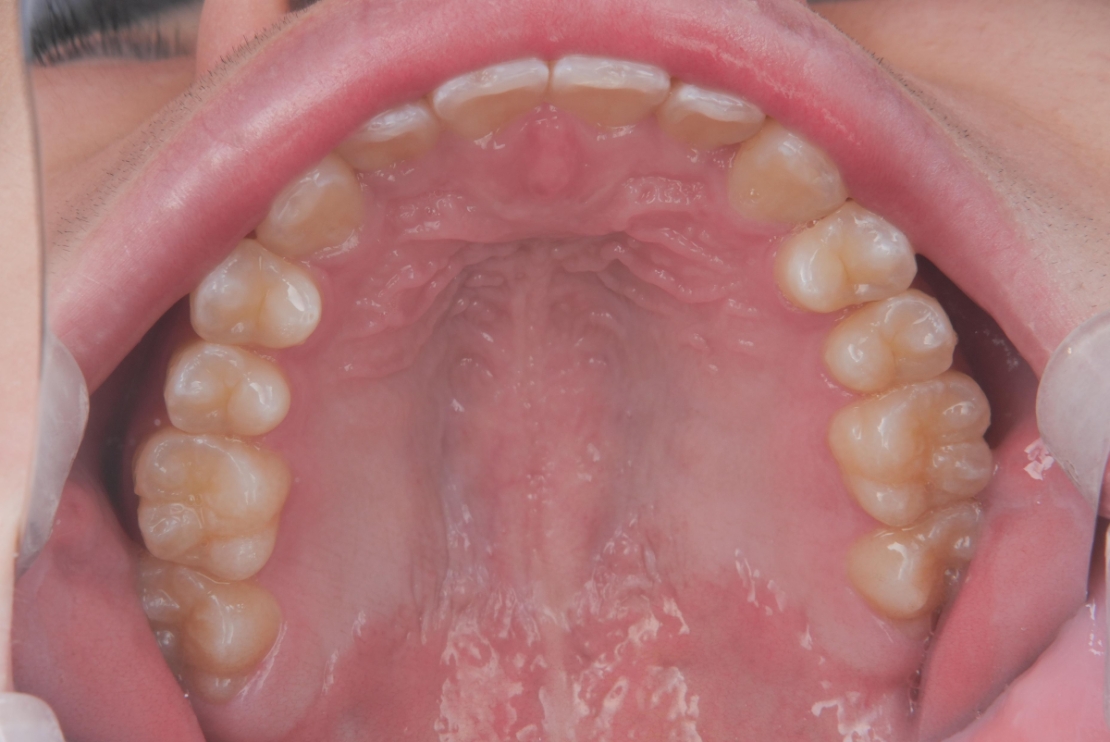

BEFORE

AFTER